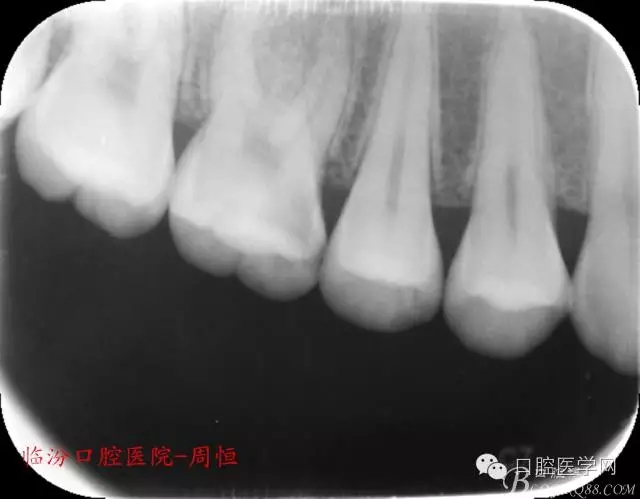

圖1 X示 術(shù)前

X 示:近中低密度陰影達(dá)髓腔,牙根未見異常。

檢查:16近中齲壞深,探痛,已露髓,冷測痛明顯,叩痛(+-),無松動(dòng)全口牙石(++),牙齦紅腫。